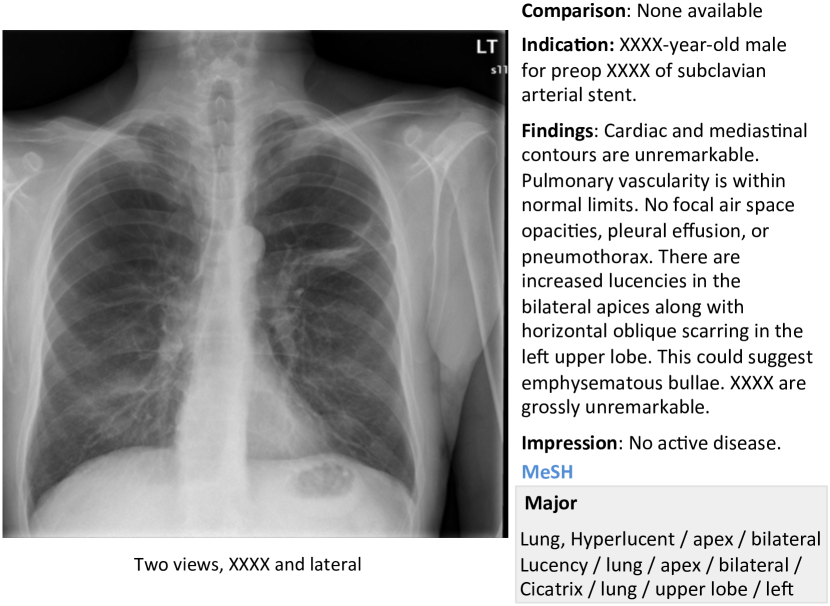

More examples of chest x-ray image, report, and annotations available on OpenI [2] is shown in Figure 7.